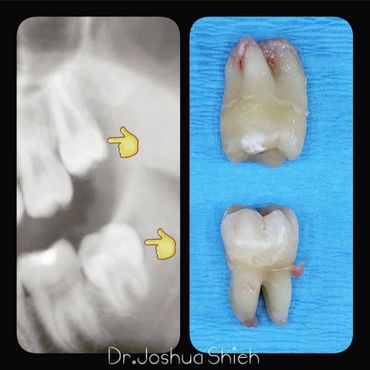

If the tooth is planned for extraction, an x-ray of the area will be taken to plan for the type of extraction.

Early Wisdom Teeth Extraction

Wisdom teeth are the third set of human molars. Unfortunately, in some cases, those teeth are impacted fully or partially in bone or soft tissue and cannot erupt causing pain, discomfort and swelling. Additionally, most people have difficulty accessing these teeth during brushing or flossing causing accelerated decay and gum problems. Wisdom teeth have also been notorious for causing crowding, improper bites and pressure when they start erupting. The arrival of these late-breaking teeth can cause trouble as they are often impacted (trapped in the jawbone) because there is not enough room for them in the mouth. Our jaws are a lot smaller than those of our early human ancestors, who needed bigger jaws and more teeth for the type of food they chewed. In most people, wisdom teeth can do more harm than good and we often recommend their removal.

It can take a long time for wisdom teeth to erupt and you may not even notice the harmful effects in your mouth until you experience sudden and severe discomfort. Cramped for room, impacted wisdom teeth grow out at odd angles or remain trapped below the gums. Adjacent teeth can become prone to decay because of the unfavourable position of the wisdom teeth.